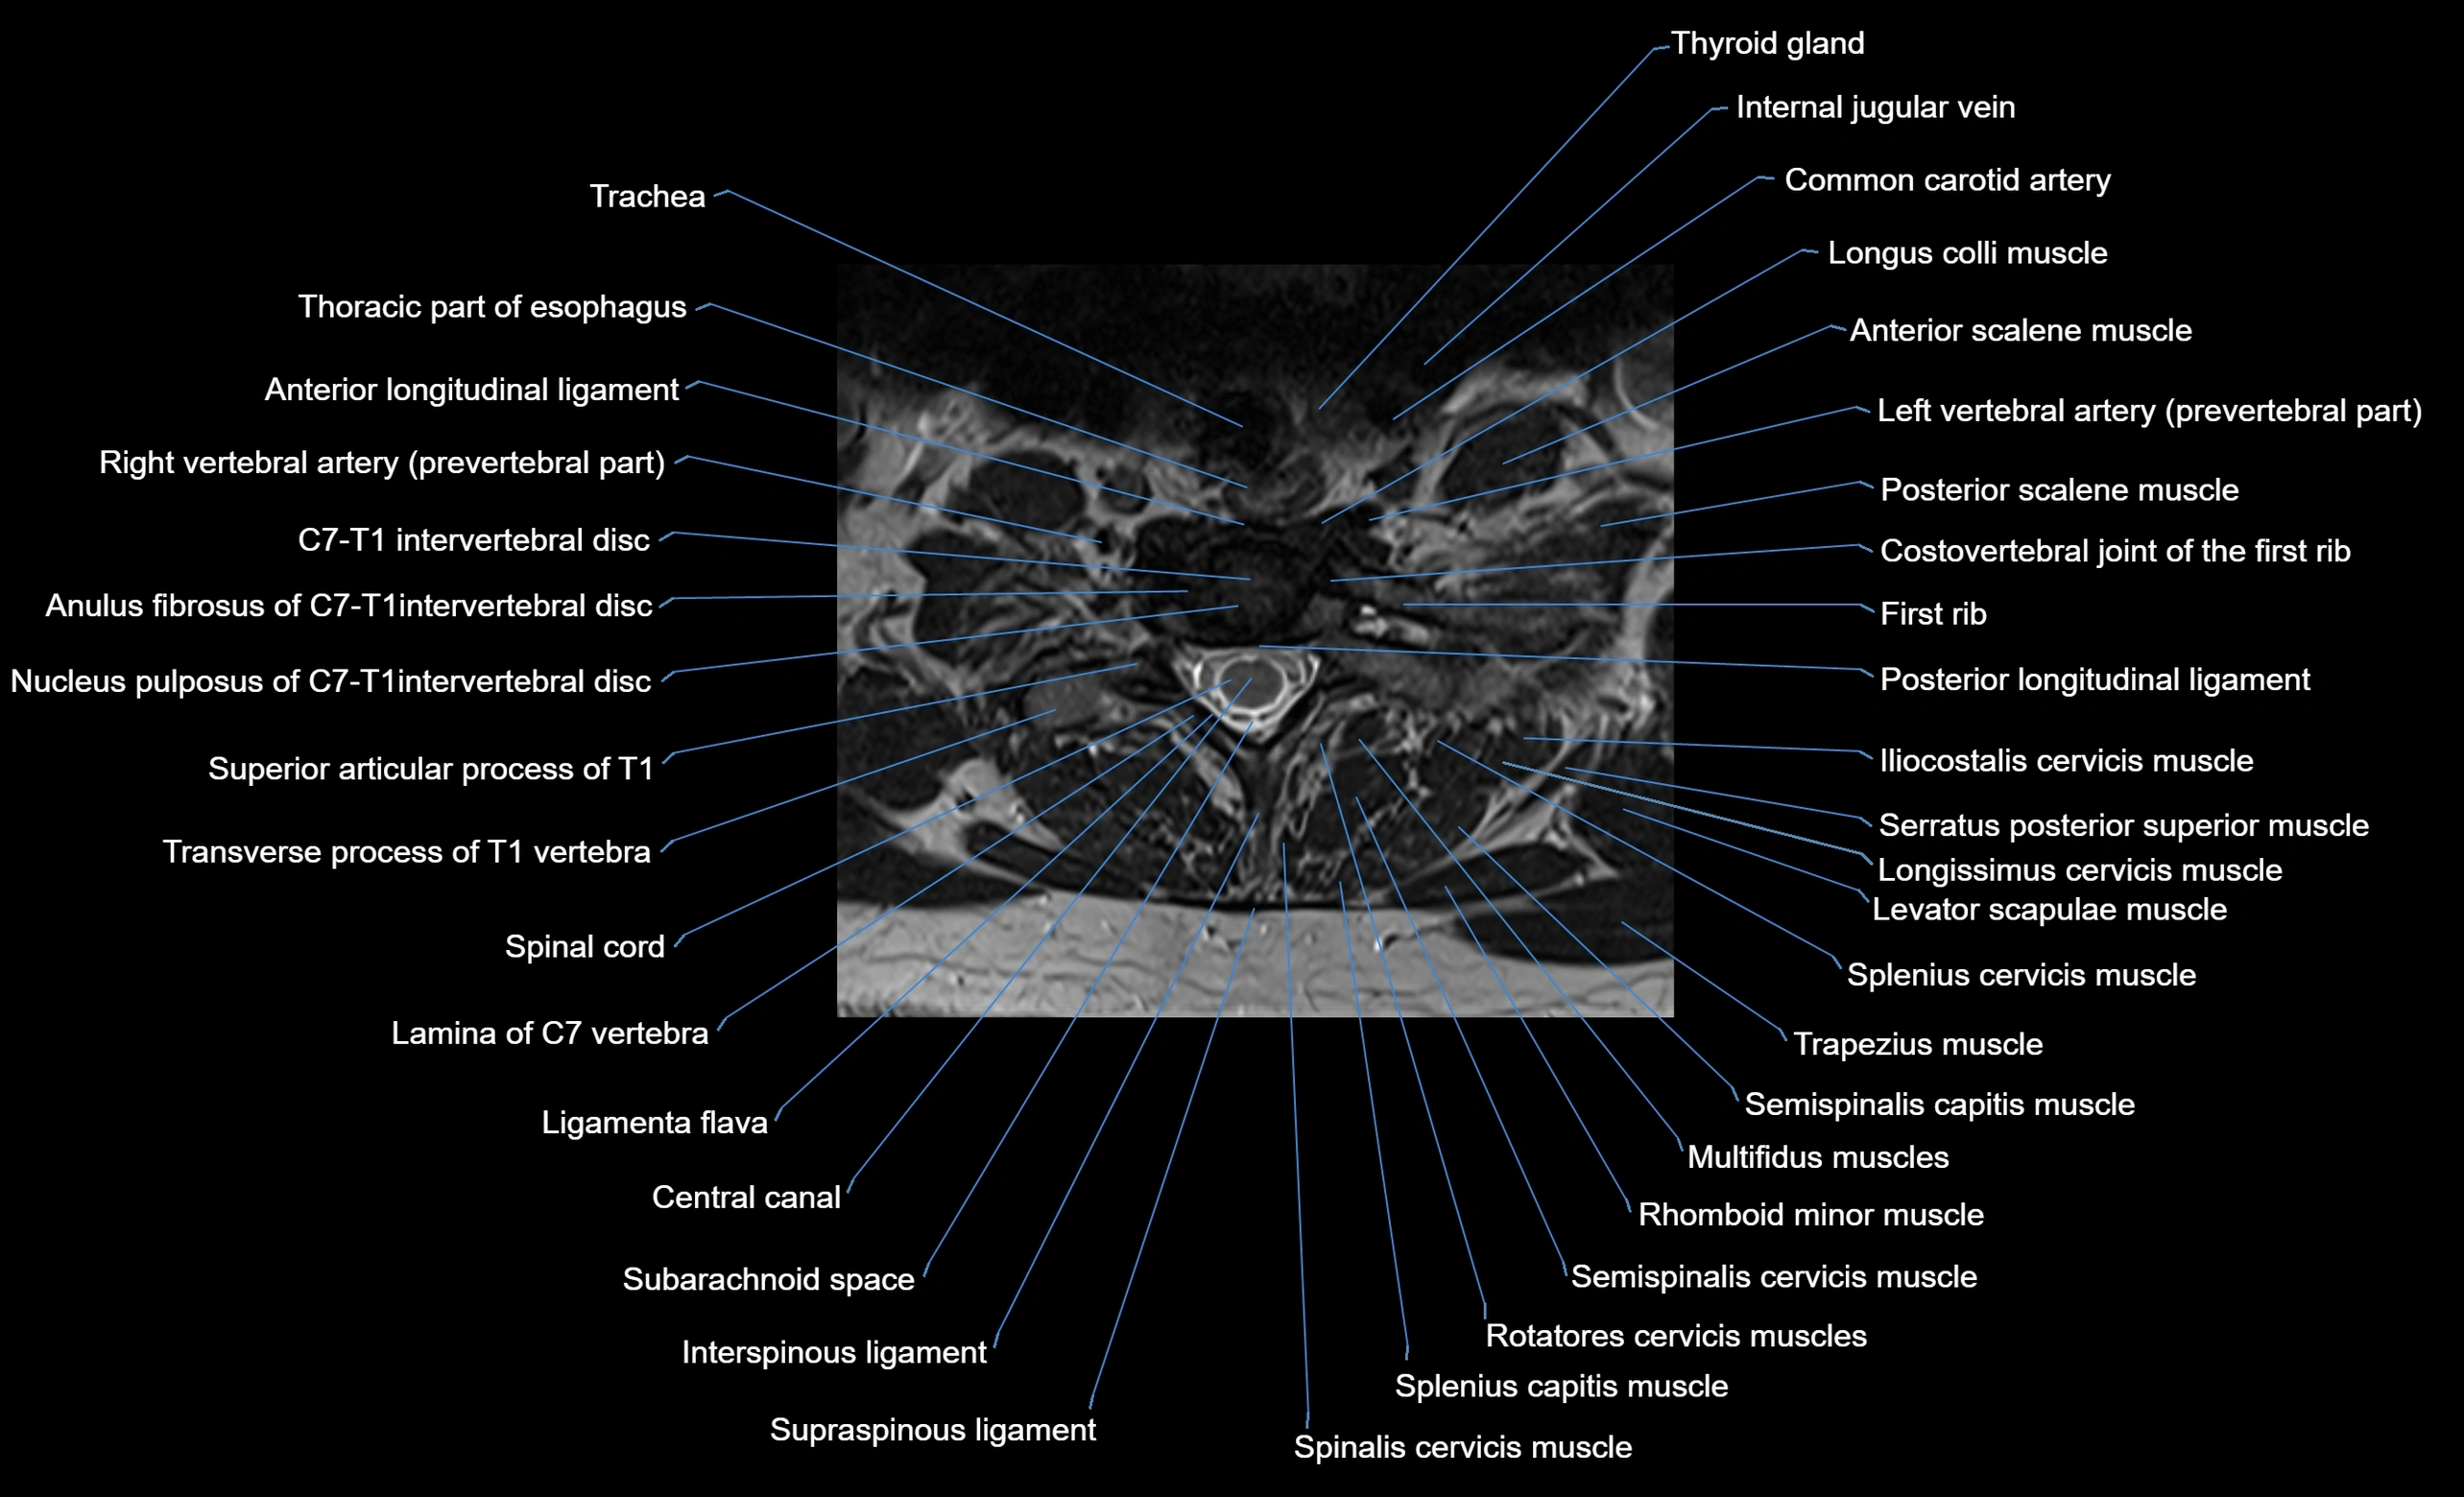

MRI image

image